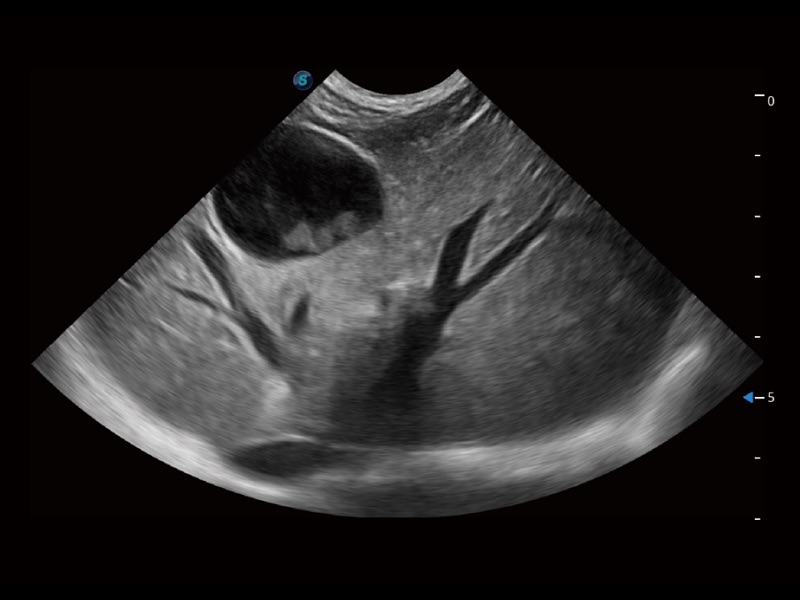

能够基于左心室壁追踪和辛普森法,自动计算射血分数,支持多个可移动点描迹,与手动测量相比,极大节省了动物医生的时间和精力。

通过360度任意调节3条M型取样线,在同一心动周期上观察心脏不同位置的运动曲线,得到准确的心功能测量数据,有效评估心肌运动及左心室功能。

实时用颜色表示心肌组织运动,观察和定量组织的运动情况,对快速检测与评估心肌的灌注和活性、电传导及心肌收缩和舒张功能等均能提供重要的诊断信息。

当心脏测量结果超出正常范围时,可实时预警提示动物医生,减少疾病漏诊概率。